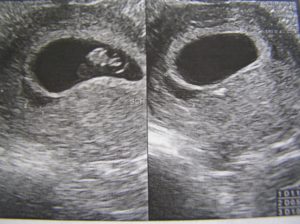

УЗИ на 9 неделе беременности

На УЗИ плода на 9 неделе определяется толщина плаценты и общее состояние пуповины. При помощи допплера, будущая мама может отметить частоту сердечных сокращений малыша. Хотя многие внутренние органы уже достаточно развиты, это не всегда можно увидеть на УЗИ на 9 неделе.

Внутренние органы крохи еще могут выступать в виде пупочной грыжи, но нет повода для беспокойства, ведь это совершенно нормальное явление.

Определить пол будущего ребенка на УЗИ ещё нельзя, однако, существуют другие способы узнать пол своего малыша. О достоверных способах мы говорили в этой статье.

На девятой акушерской неделе беременности ультразвуковое обследование позволяет услышать биение сердечка ребеночка. Помните, что акушерский срок немного отличается от эмбрионального возраста плода. Это примерно 1-2 недели.

В норме сердце плода бьется 140-160 ударов в секунду. При обследовании частота может повышаться. Ведь это стресс, и малыш волнуется. Также в такой ситуации может сокращаться матка.

Но диагноз «гипертонус» ставится только в том случае, если сокращение стенок матки происходят постоянно, а не во время УЗИ.

В данный срок специалист УЗИ оценивает состояние жёлтого тела, которое вырабатывает гормон прогестерон. Сейчас недостаток этого вещества крайне опасен и может привести к прерыванию беременности.

Ультразвуковоеисследование плода на сроке девятаяакушерская неделя беременности (перваянеделя третьего акушерского месяца)проводят только при специальныхпоказаниях. В данное время обычноврач-гинеколог это исследование неназначает.

Половые признаки внутриутробногомалыша разглядеть на фото9 недели беременностипрактически не представляется возможным.Однако можно увидеть, одноплодная илимногоплодная беременность у будущеймамы. Данный методисследования сейчас малоинформативен.

Плановое ультразвуковое исследованиев женской консультации обычно проводятв конце первого триместра беременности,на сроке одиннадцатая или двенадцатаянеделя.